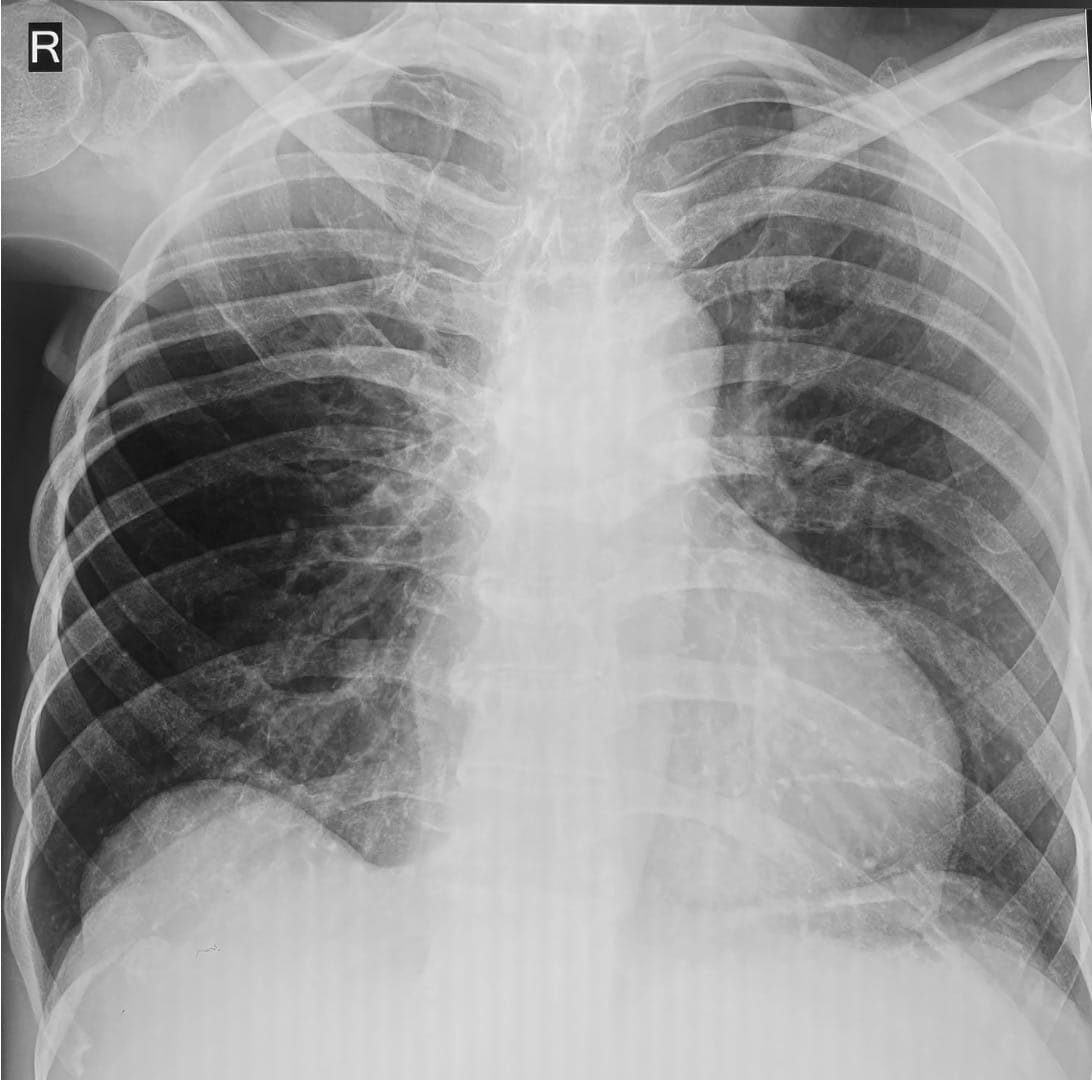

A 67-years old patient presented without any prior diagnosis to a pulmonologist for mild breathlessness. The chest radiograph was unusual.

Thoughts?

- Emphysema

- Right main bronchus obstruction

- Poland syndrome

- Constrictive bronchiolitis